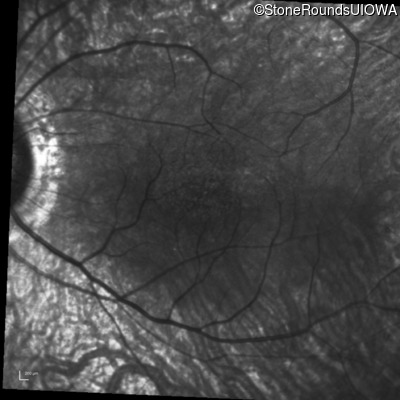

Infrared Fundus Photograph - Right - 20/40

Exemplar